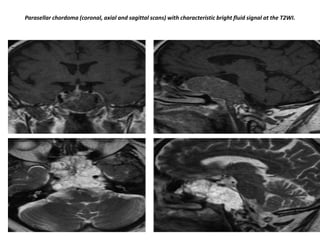

Parasellar chordoma (coronal, axial and sagittal scans) with characteristic bright fluid signal at the T2WI.

Chordomas are the most common lesions of the clivus, also a favored location for metastases and chondrosarcomas. his

patient has a normal pituitary gland. Posterior to this is a large, fungating mass positioned at the level of the clivus. The CT

shows some calcifications in this area. The differential diagnosis for this mass would be chondroma or chondrosarcoma.

Chordomas tend to occur in the midline, whereas condrosarcomas tend to occur off the midline.